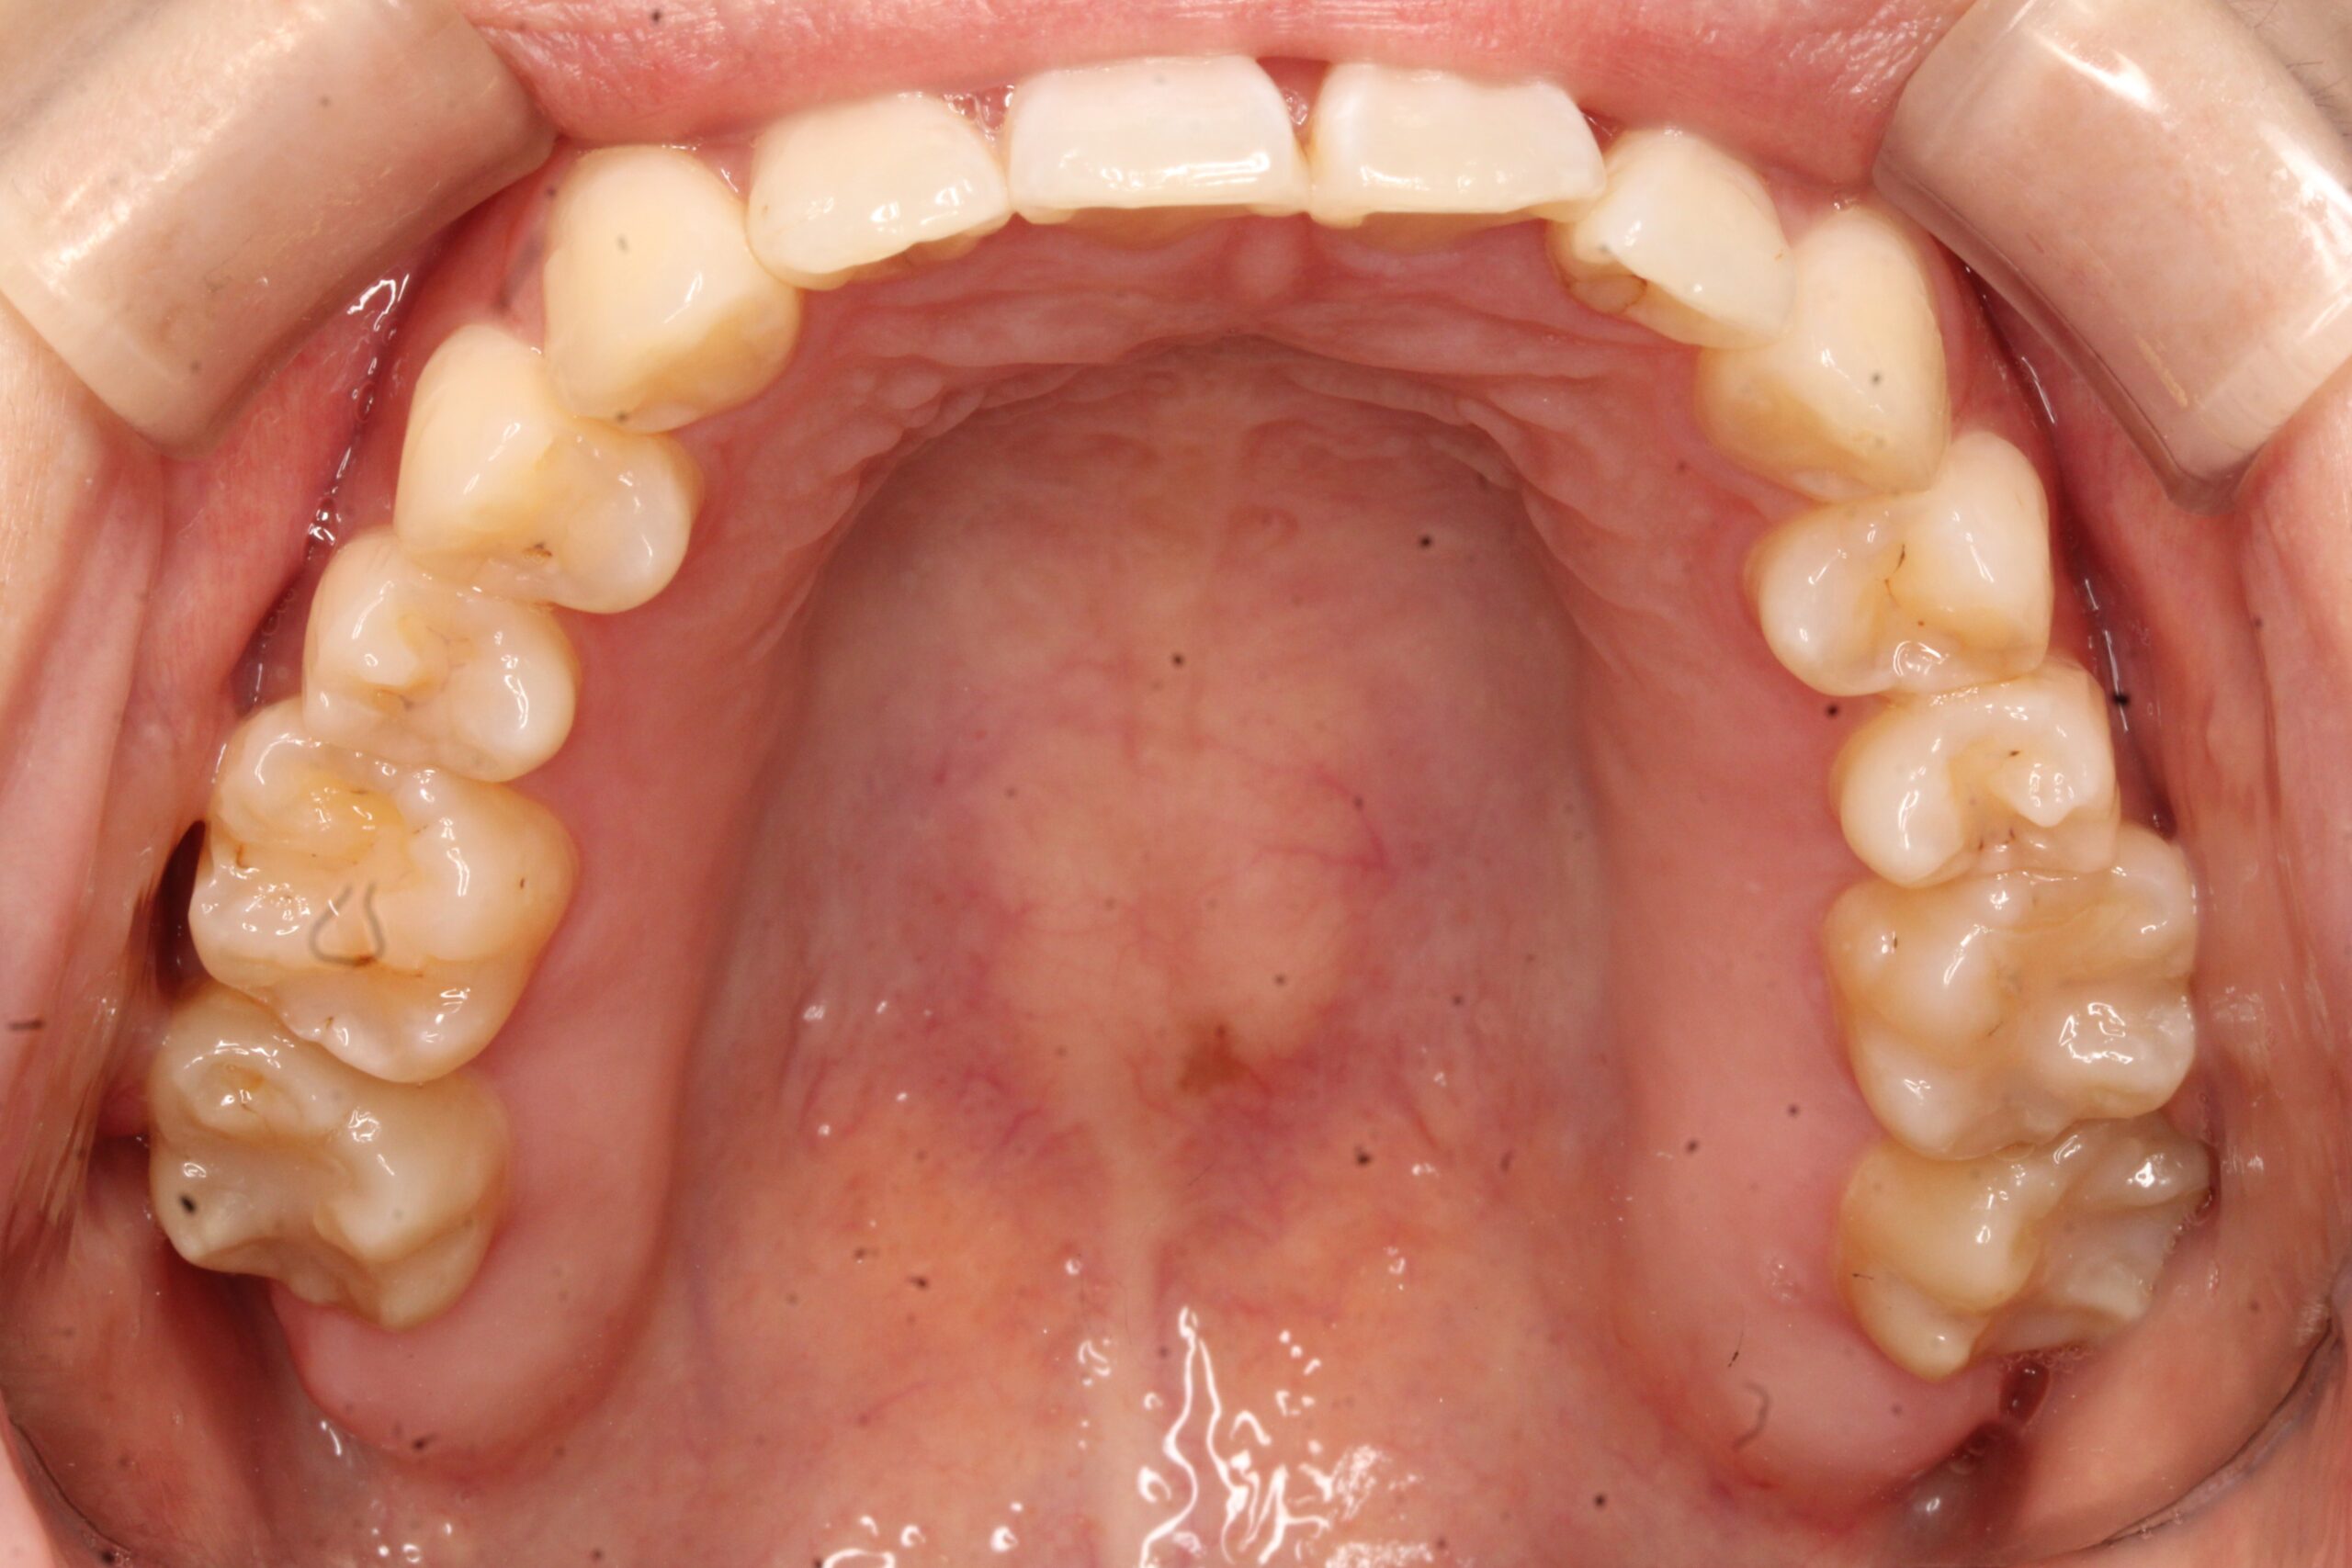

矯正術前:下顎

矯正術後:下顎